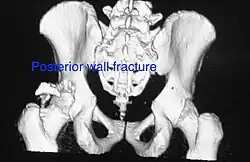

Both column fracture showing floating weight bearing dome -

Both column fracture after fixation with screws and plates -